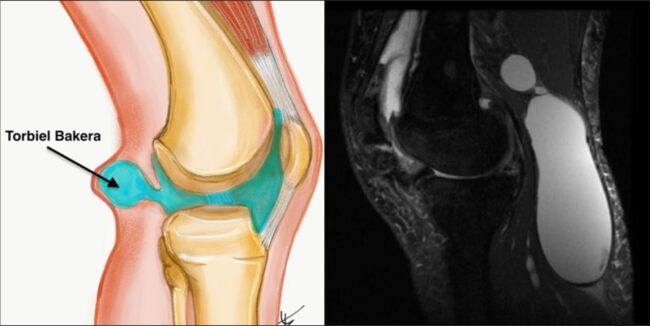

Jak się leczy cystę Bakera? Cysta Bakera, znana również jako torbiel podkolanowa (ang. popliteal cyst), to dość częste schorzenie stawu kolanowego. Bywa powodem niepokoju pacjentów z racji pojawienia się miękkiego guza w dole podkolanowym. U dorosłych pacjentów najczęściej występuje wtórnie do chorób zwyrodnieniowych i stanów zapalnych stawu kolanowego. Przedstawię aktualny stan wiedzy dotyczący etiologii,…